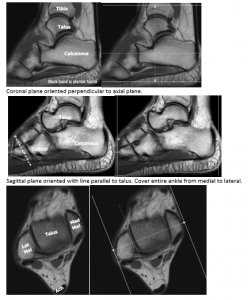

Ankle

Orient axial plane to axis of calcaneus.

Coronal plane oriented perpendicular to axial plane.

Sagittal plane oriented with line parallel to talus. Cover entire ankle from medial to lateral.